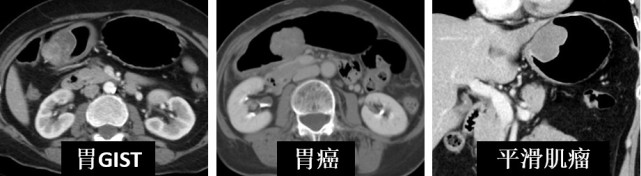

第二点,影像学有一个术语叫“异病同征,同病异征”。如图所示:

图片(异病同征示例)

这一排是胃的肿瘤,有胃肠间质瘤GIST、胃癌、平滑肌瘤,看起来都是球形的,但是它们是完全不同的病,治疗方法也完全不一样。

图片(同病异征示例)

这一排则都是胃癌,左边长得像球,中间的像个火山口,右边的则是整个弥漫的增厚,所以同样的肿瘤也可能长成不一样的形态。

这个时候影像医生就需要结合患者症状、病史和各种检查结果再去做进一步的判断。所以影像科医生是诊断医生,而不是只看片子的。如果有影像医生询问您相关的病史,是为了得到一个准确的判断,大家一定要详尽如实地跟医生们介绍。